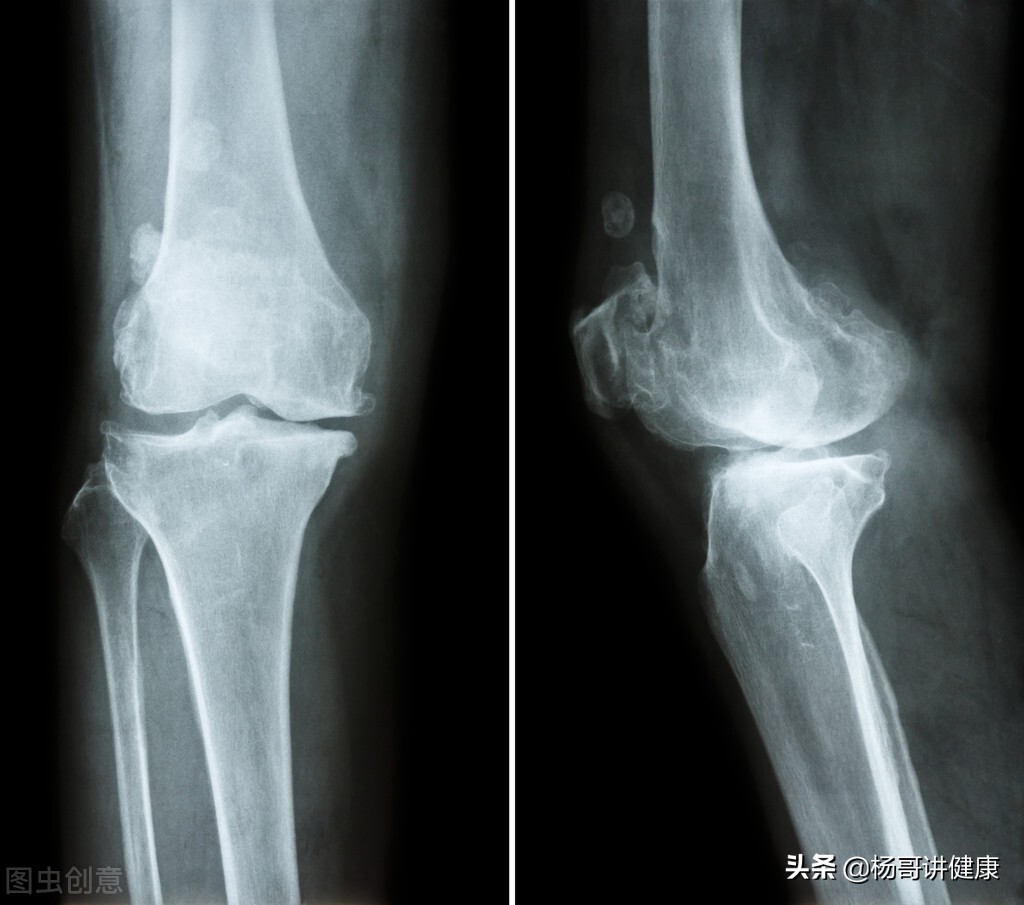

#膝关节长骨刺怎么治疗?#当20年前有人问膝关节长骨刺怎么治疗时,还是一种普遍现象,那个时候X光片还是一家独大,用它就能照出骨刺来。而如今,价格便宜的X光片几乎无人问津,即使CT也被冷落一旁,核磁已经从当时的“王谢堂前燕”,飞入了“寻常百姓家”,管你是拉车的、烧碳的,还是搞电气焊的,只腰你膝关节疼,上来就是核磁,出来的都是半月板撕裂、交叉韧带断裂、关节腔积液、髌骨软化等等,什么狗屁骨刺,早OUT了吧,你这病也太落后了吧!